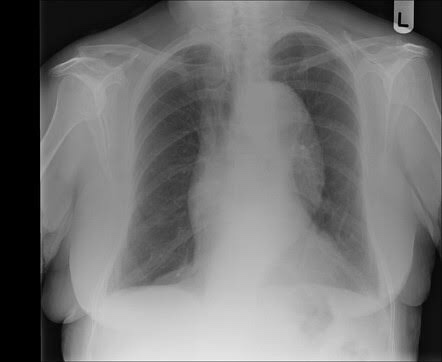

• PA and lateral chest x-rays demonstrate markedly enlarged cardiac silhouette.